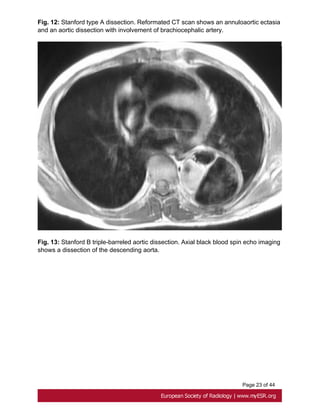

the dissection and any involvement of aortic branch vessels. Fig. 12 on page 21

Fig. 12: Stanford type A dissection. Reformated CT scan shows an annuloaortic ectasia

and an aortic dissection with involvement of brachiocephalic artery.

Fig. 13: Stanford B triple-barreled aortic dissection. Axial black blood spin echo imaging

shows a dissection of the descending aorta.

Page 9 of44 or leak at proximal and distal graft anastomoses and at coronary reimplantation site [17]. Fig. 8 on page 17, Fig. 9 on page 18, Fig. 10 on page 19 • Aortic dissection Aortic dissection is characterized by separation of the layers of the aortic media initiated by a primary intimal tear[10]. Stanford type A dissection, which involves the ascending aorta, should be treated as a surgical emergency. Uncomplicated Stanford type B dissection, which is confined to the aortic arch and the descending aorta, can be treated with medical therapy[18]. Fig. 11 on page 20 ECG-gated CT is the first line investigation in acute dissection. Procedure include a non contrast study to look for intramural hematoma, and a contrast study. CT shows the false lumen which is separated from the true lumen by an 'intimal flap", and the extension of the dissection and any involvement of aortic branch vessels. Fig. 12 on page 21 MRI is recommended for long-term for follow up patients with Stanford B dissection, to appreciate changes in the size of the dissected aorta .Its use in the acute dissection is limited by a prolonged study duration [19]. Fig. 13 on page 23 • Bicuspid aortic valve Prevalence of bicuspid aortic valve in Marfan patients is about 5% whereas it is 1-2% in the general population. A bicuspid valve has two cusps instead of three; most commonly they are unequal size because of congenital fusion of one of the valves commissures [20]. Bicuspid aortic valve is generally detected by transthoracic echocardiography. ECG gated and contrast-enhanced CT shows two completely developed cusps and commissures [21]. Fig. 14 on page 23 • Mitral valve About 65 % of patients with Marfan's syndrome have mitral valve prolapse. Compared with myxomatous disease patients, Marfan patients have longer and thinner mitral valve leaflets, less posterior leaflet prolapsed and more anterior or bileaflet prolapse[22]. • Pulmonary artery

Page 23 of44 Fig. 12: Stanford type A dissection. Reformated CT scan shows an annuloaortic ectasia and an aortic dissection with involvement of brachiocephalic artery. Fig. 13: Stanford B triple-barreled aortic dissection. Axial black blood spin echo imaging shows a dissection of the descending aorta.